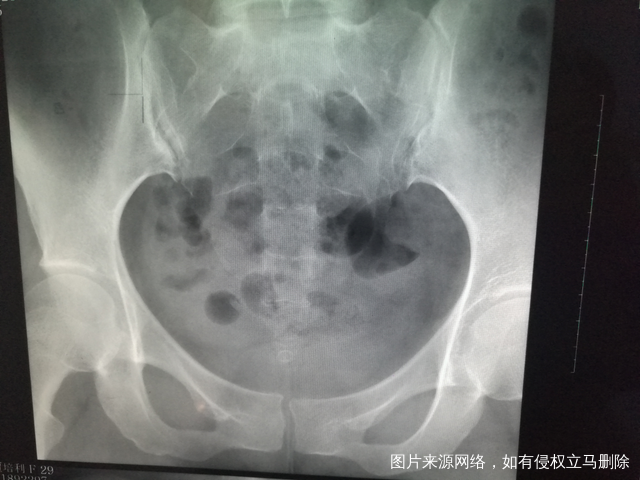

做完输卵管造影第六天了小腹还是感觉沉甸甸的如

可以热敷腹部,如果有发热,腹痛加剧,白带量多,有异味,随时就医